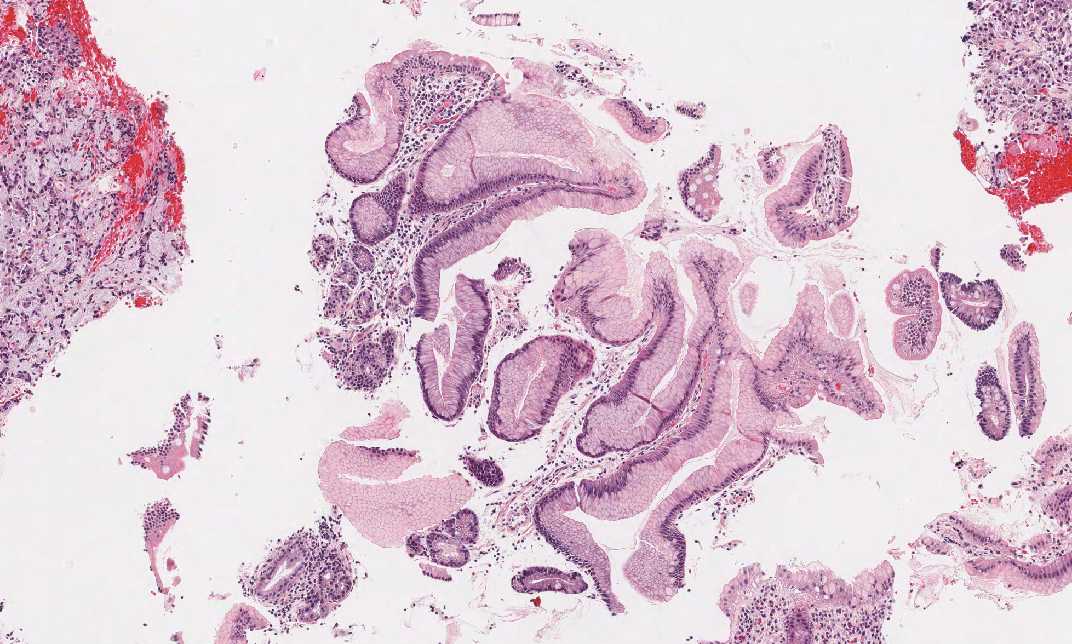

Area 1: This is the area with gastric mucosa fragments. Note that intestinal metaplasia is present in some of the fragments.

Area 2: This is the area of residual gastric mucosa with chronic atrophic gastritis and intestinal metaplasia.

• There are residual gastric mucosa with intestinal metaplasia which helps to identify this specimen as stomach (Area 1). These are areas with atrophic gastritis and intestinal metaplasia.